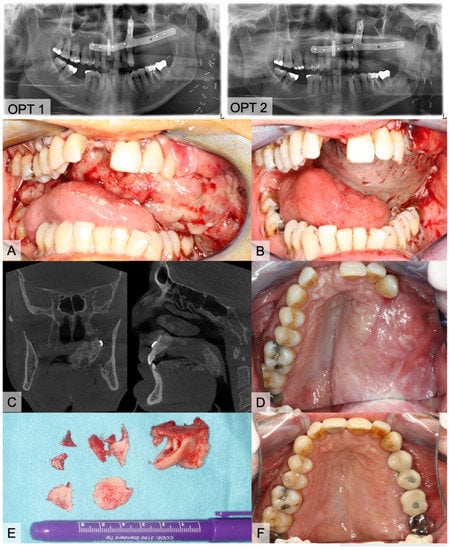

The evaluated medical records of the HO+ group showed clinical symptoms in 10 cases with swallowing difficulties (n = 5), trismus (n = 3), and palpable bony masses in level I (n = 2). Clinical complaints occurred after an average time of 6.3 months. Surgical intervention with a removal of calcification was only necessary in five cases. One of the patients (Figure 7) had a two-staged, virtually planned mono-segmental maxillary reconstruction after previous resection of a recurrence of a odontogenic kerato-cyst (OKC). Early after flap transfer there was an extensive overgrowth of granulation tissue with subsequent periosteal ossification in the area of the palate and parts of the vascular pedicle (HO type 4). He suffered from severe dyspnea and dysphagia, prompting the surgical removal of the granulation tissue and parts of the heterotopic ossification. As a temporary wound closure, the defect was covered with a split skin graft and a screw-fixed dressing plate for five days. With further progress, a modelling osteotomy was performed simultaneously with the insertion of dental implants. Histopathologic evaluation of the tissue specimen confirmed the presence of mature bone tissue (Figure 7).

Figure 7. Images of an 54-year-old, healthy male who underwent subtotal hemi-maxillectomy due to a second recurrence of an odontogenic kerato-cyst (OKC). After more than one year later, we performed a virtually planned mono-segmental FFF transfer without a skin paddle for maxillary reconstruction (OPT 1). Three days after discharge, he consulted the emergency unit with progressive dyspnea and fear of asphyxiation in dorsal position. Clinical inspection showed large masses of soft and vulnerable granulation tissue (A). After carefully removing the tissue, we covered the bone with a split skin graft from the thigh (B). Six months later, we planned implantological rehabilitation. OPT and CBCT were accomplished and presented large bone masses at the palate (C, OPT 2). Clinical impression is shown on image (D). Prior to the insertion of four dental implants, we molded the FFF and removed bone masses (E). Implants were exposed four months later. Figure (F) shows the final prosthetic rehabilitation.